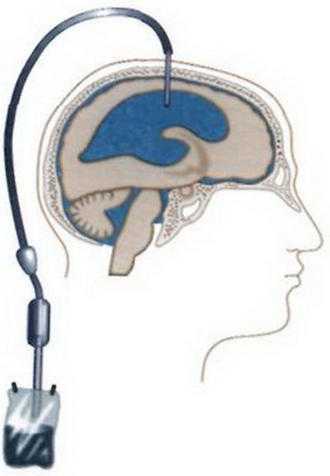

Вентрикуло-перитонеальный шунт: Показания и применение